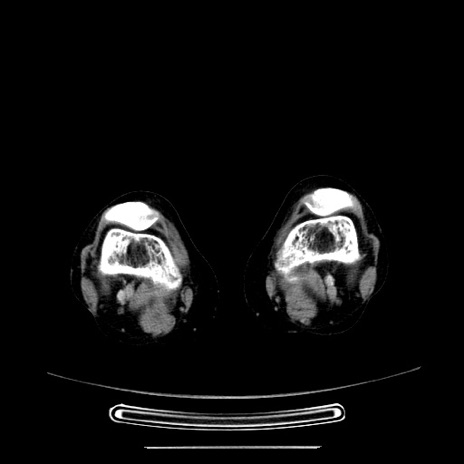

症例5(横断像)

【症例】70歳代女性

【主訴】お腹が張る

【現病歴】1週間くらい前から腹部膨満の自覚あり。昨日夜から増悪したため、本日救急外来受診。

【身体所見】意識清明、BT 36.5℃、BP 165/106mmHg、HR 80bpm、SpO2 98%、腹部:膨満、軟、自発痛・圧痛なし、触診にて不快感あり、腸蠕動音:減弱

【データ】WBC 12600、CRP 1.04